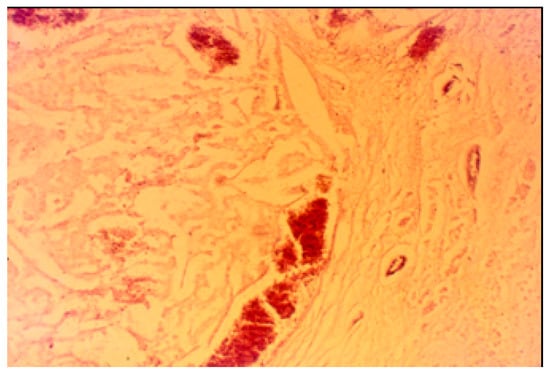

3.2. Histopathological Findings